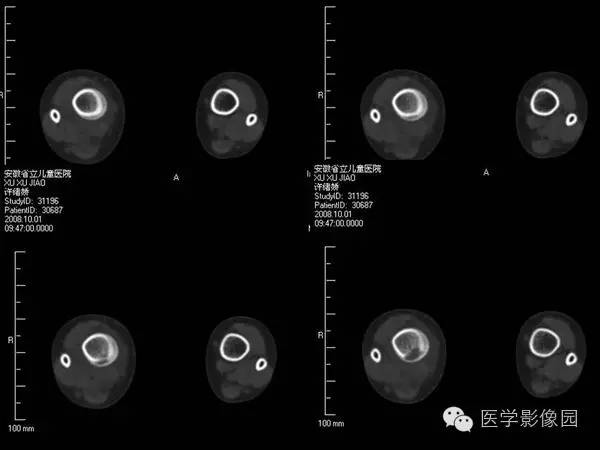

【病例】浆细胞性骨髓炎1例X线及CT影像表现